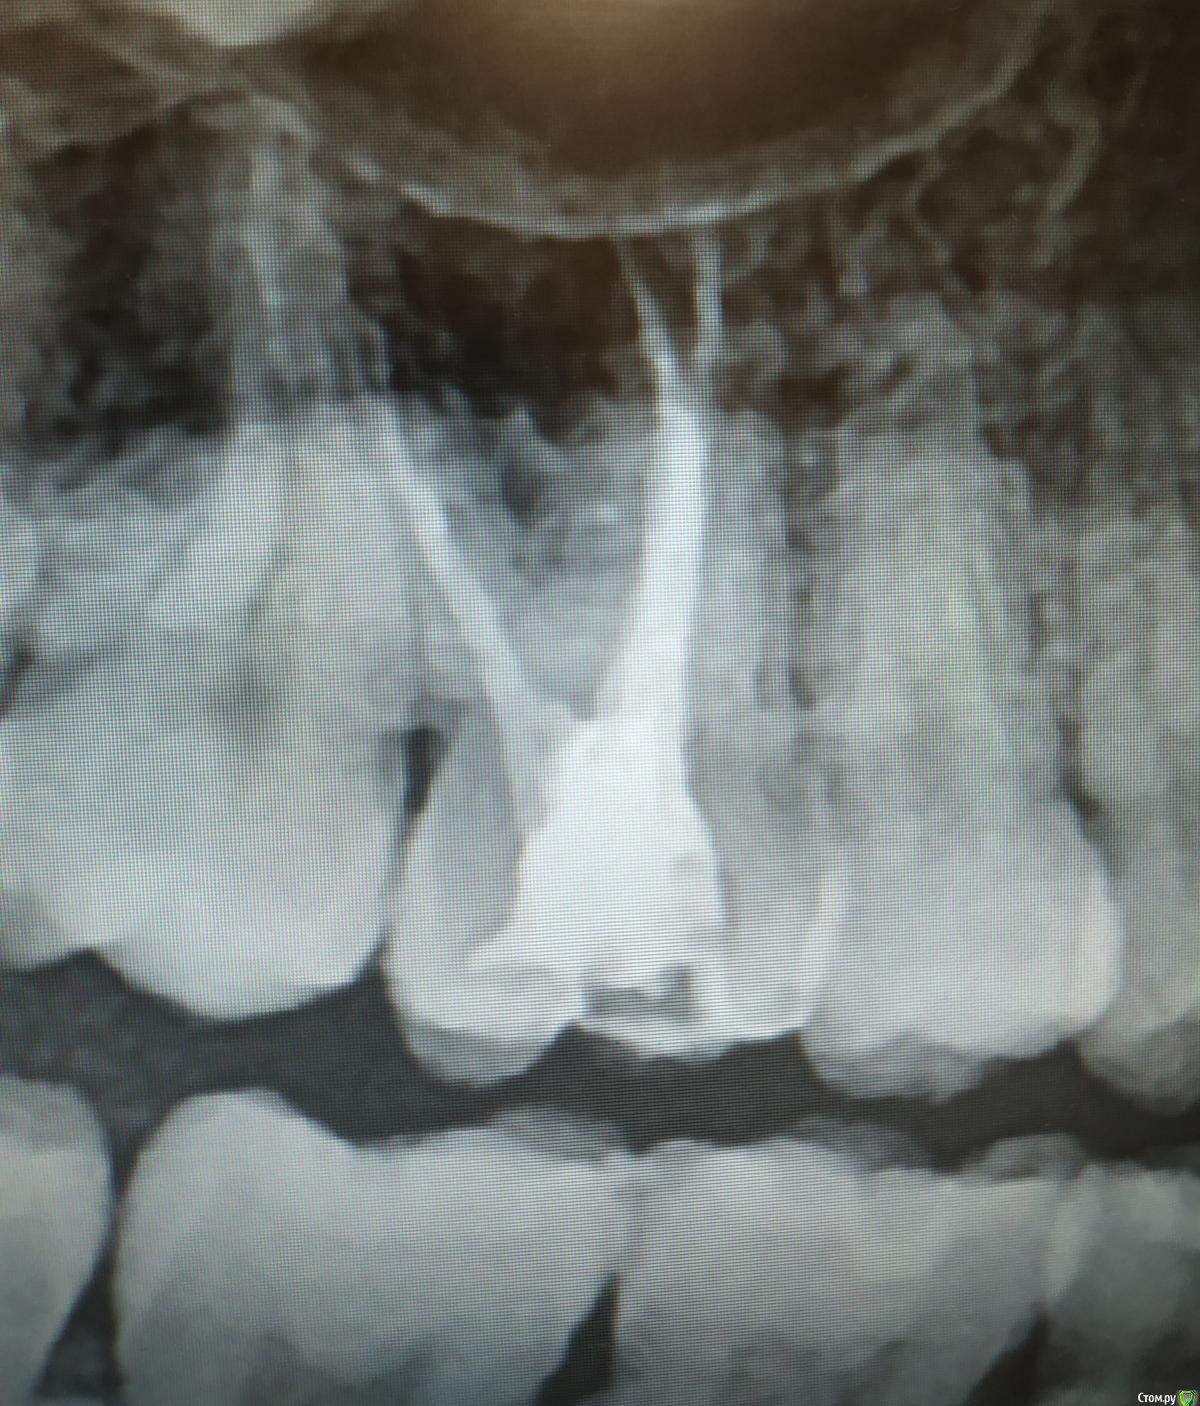

Mashaa1337 Опубликовано 10 сентября, 2019 Автор Поделиться Опубликовано 10 сентября, 2019 (изменено) Зуб 1.1. Ранее лечен по поводу кариеса. Со слов пациентки : появилась резкая боль , усиливающаяся при накусывании, опухла десна. Обратилась в дежурную стоматологию , там ей вскрыли полость зуба и оставили зуб открытым, пациентка сказала, что выделялся гной. На следующий день пришла ко мне. При осмотре отмечается отек по переходной складке, верхняя губа отечна ,подвижность зуба 1 степени, перкуссия безболезненна. Какой писать диагноз ? Можно ли в данном случае ввести в каналы метапекс? Изменено 10 сентября, 2019 пользователем Mashaa1337 Ссылка на комментарий

vse32 Опубликовано 10 сентября, 2019 Поделиться Опубликовано 10 сентября, 2019 Диагноз - обострение хронического периодонтита. Ну или как там по вновь введенной номенклатуре требуют писать.Вести соответственно периодонтиту. Мех, мед обработка, кальций, времянка на 1- 2 недели. Далее по обстоятельствам. Либо замена кальция, либо постоянная обтурация. Ссылка на комментарий

Mashaa1337 Опубликовано 11 сентября, 2019 Автор Поделиться Опубликовано 11 сентября, 2019 По мкб есть К04.5 хронический апикальный периодонтит, а обострения хронического нет. Можно ли написать К04.7 периапикальный абсцесс без свища? Ссылка на комментарий

Vladimirov Опубликовано 11 сентября, 2019 Поделиться Опубликовано 11 сентября, 2019 К04.4 не? 1 Ссылка на комментарий

ЛанаМ Опубликовано 12 сентября, 2019 Поделиться Опубликовано 12 сентября, 2019 Классификация дурная и не соответствующая клинике. к 04.4 так-то острый периодонтит, который встречается редко, в основном все обострение хронического. Думаю,что если есть отек и гиперемия на слизистой, то можно писать абсцесс. Если нет, то пишу как острый периодонтит. Ссылка на комментарий